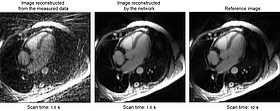

心動周期某一階段的心臟 MR 影像。左:直接從測量數(shù)據(jù)重建的影像;中:使用最近開發(fā)的方法得到的結(jié)果;右:參考影像。參考影像所需的測量時間是新方法的六倍以上。

PTB專門開發(fā)了一個迭代網(wǎng)絡(luò)來重建動態(tài)心臟影像。在訓練階段,這個過程結(jié)合了用于成像的物理模型和先前關(guān)于網(wǎng)絡(luò)學習的影像數(shù)據(jù)結(jié)構(gòu)的知識。心臟功能的 MR 影像隨后會顯示心動周期不同階段的心臟狀況??梢允褂脭?shù)據(jù)的這個時間分量來確保訓練的最佳效率。

這種方法可應用于心臟病患者,然后進行評估。它還與傳統(tǒng)的迭代重建程序以及其它的機器學習方法進行了比較。由此開發(fā)出的網(wǎng)絡(luò)獲得了比傳統(tǒng)方法更好的結(jié)果(信噪比達 6 dB,相對誤差達–47 %)。此外,這種網(wǎng)絡(luò)產(chǎn)生的結(jié)果類似于通過同樣基于神經(jīng)網(wǎng)絡(luò)的另一種方法獲得的結(jié)果。另外,PTB 的程序僅使用 10% 的可訓練參數(shù)就能夠做到這一點,這證明了這種新方法的魯棒性和效率。